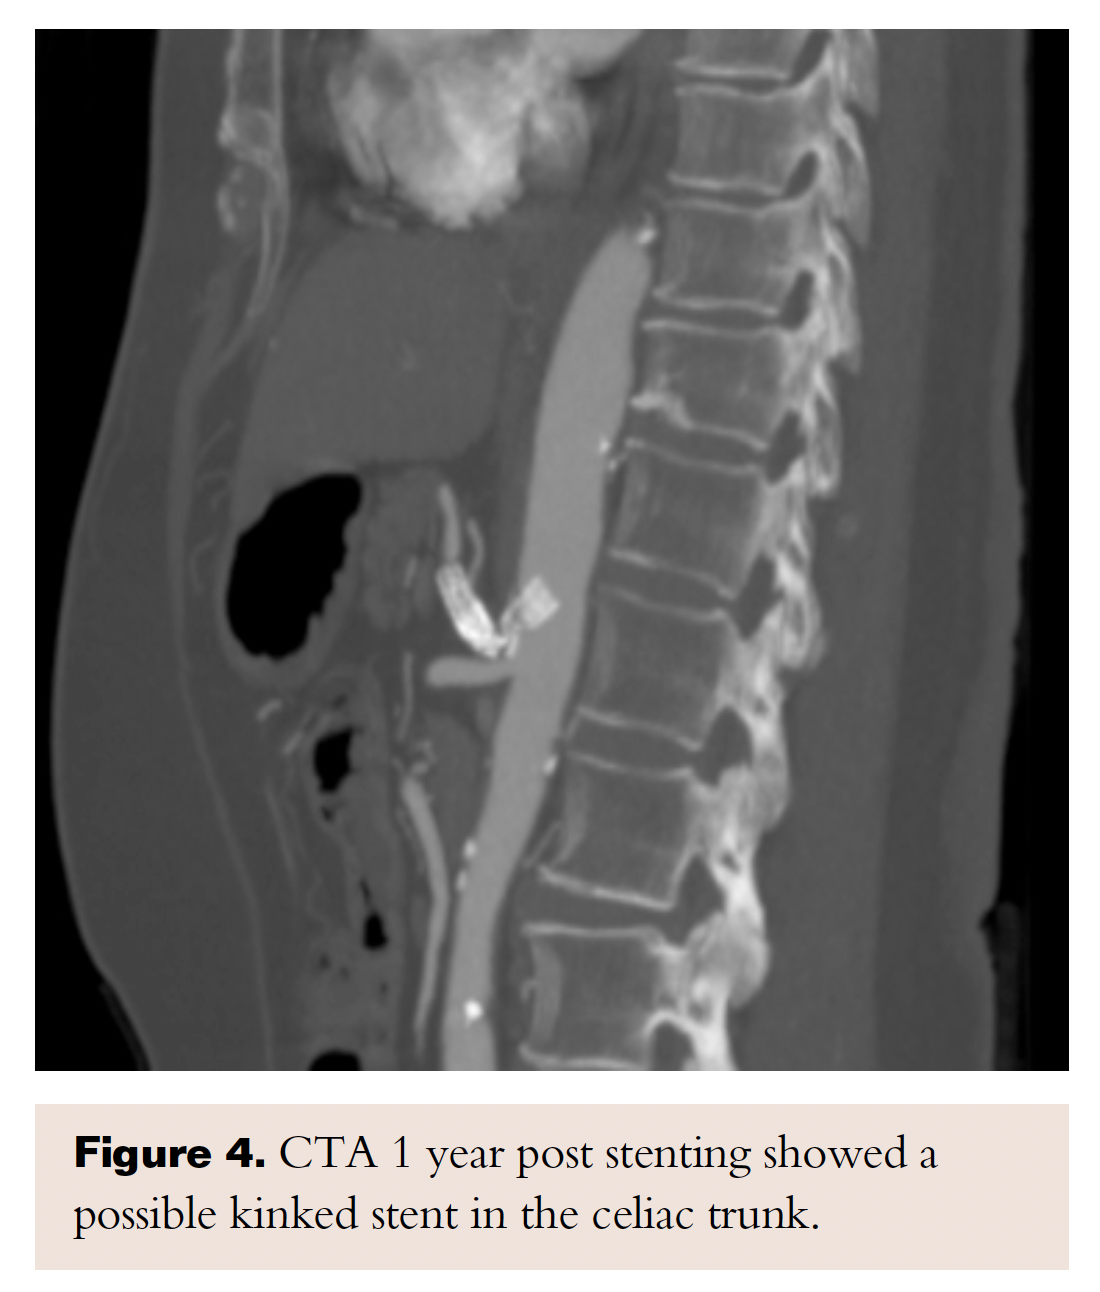

A few days after the procedure, the patient’s gastrointestinal symptoms started resolving; first, her pain was completely gone and then her appetite started to improve. At 1-year follow-up, she remained asymptomatic and regained 25 lb. Repeat CTA for right upper-quadrant pain and elevated lactic acid showed a significant distention of the common bile duct and mild intrahepatic biliary duct dilatation. The CT angiogram also showed a possible kinked stent in the celiac trunk; however, the enhancement of the distal celiac branches were consistent with patency and the patient stayed asymptomatic after the biliary stasis episode resolved (Figure 4). At 2-year follow-up exam, she had maintained her normal weight and remained completely asymptomatic.